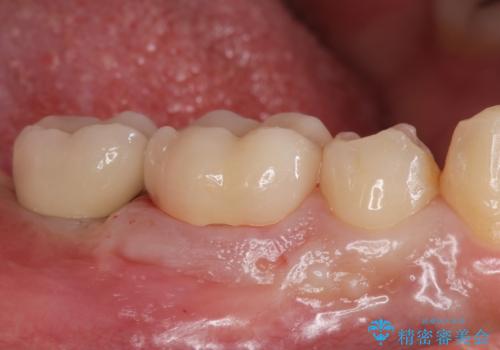

白くて綺麗な被せ物が入りました。

インプラントを入れた後は定期的なメンテナンスが必要になります。